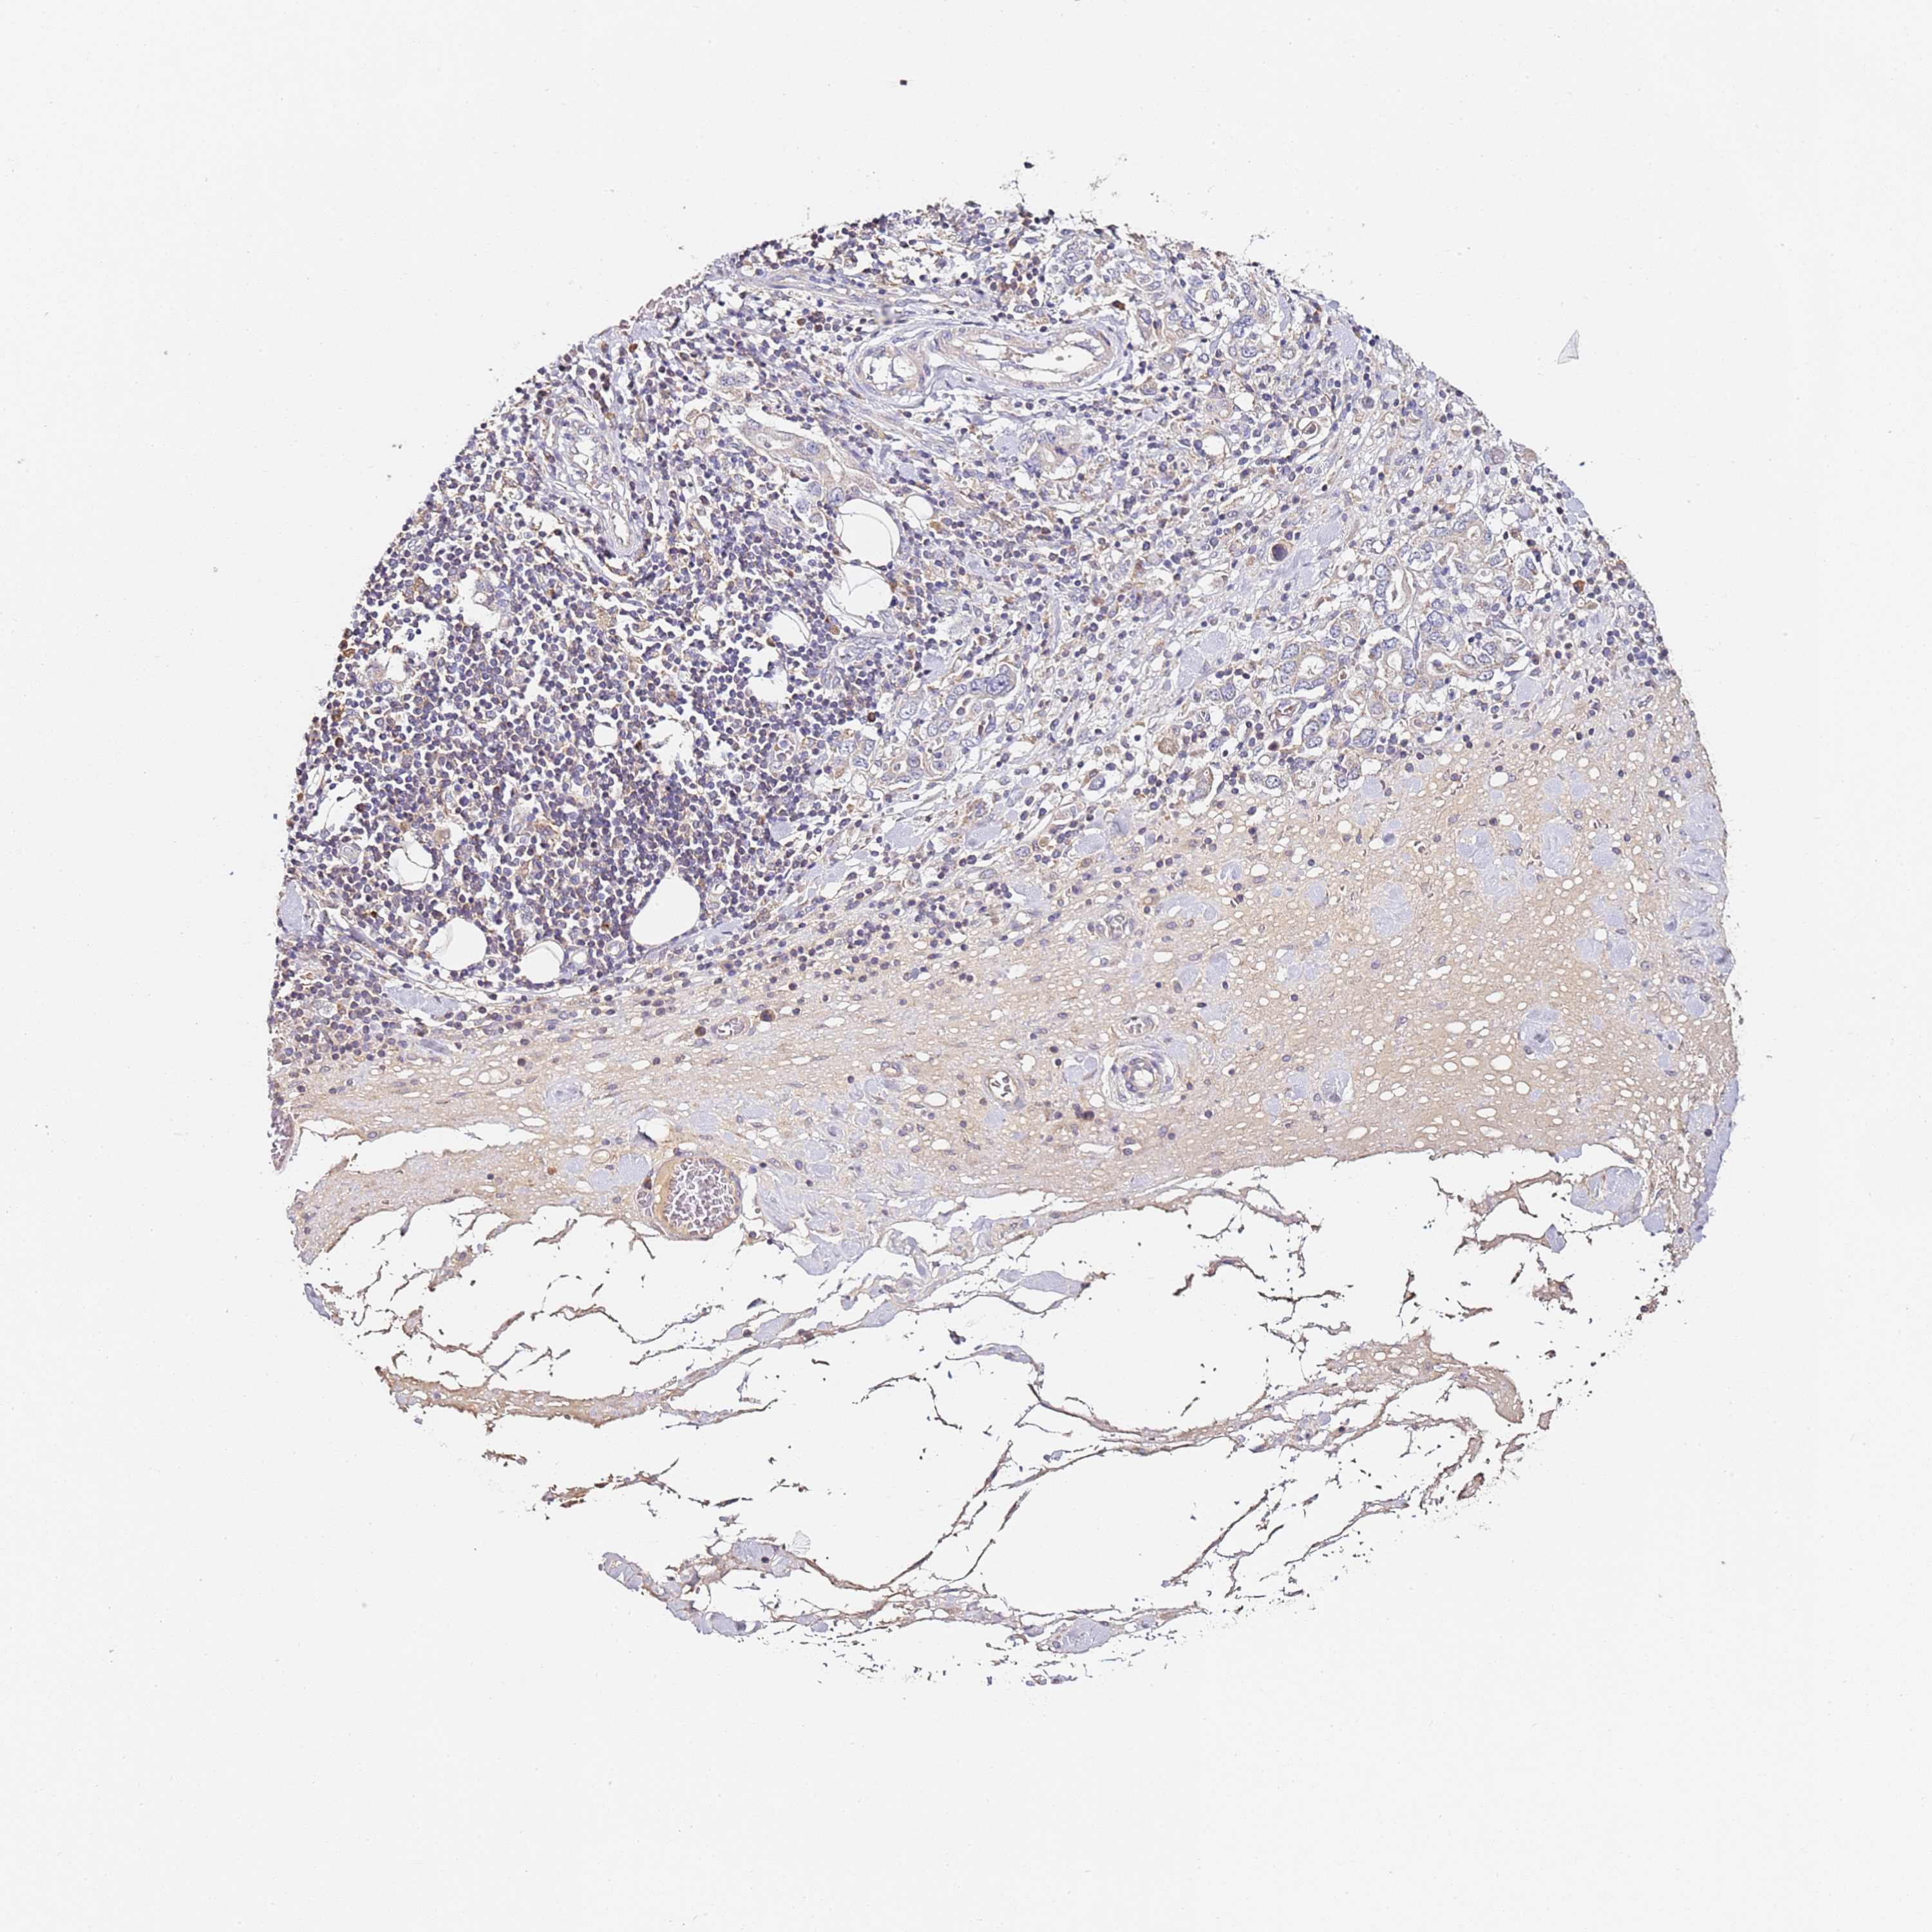

STOMACH CANCER - Protein expressioni

A mouse-over function shows sample information and annotation data. Click on an image to view it in a full screen mode. Samples can be filtered based on level of antibody staining by selecting one or several of the following categories: high, medium, low and not detected. The assay and annotation is described here.

Antibody stainingi

Antibody staining in the annotated cell types in the current human tissue is reported as not detected, low, medium, or high, based on conventional immunohistochemistry profiling in selected tissues. This score is based on the combination of the staining intensity and fraction of stained cells.

Each image is clickable and will lead to virtual microscopy that enables deeper exploration of all samples and also displays staining intensity scores, fraction scores and subcellular localization as well as patient and tissue information for each sample.

Antibody HPA047459

Staining

High

Medium

Low

Not detected

Intensity

Strong

Moderate

Weak

Negative

Quantity

>75%

75%-25%

<25%

None

Location

Nuclear

Cytoplasmic/membranous

Cytoplasmic/membranous,nuclear

Adenocarcinoma, NOS